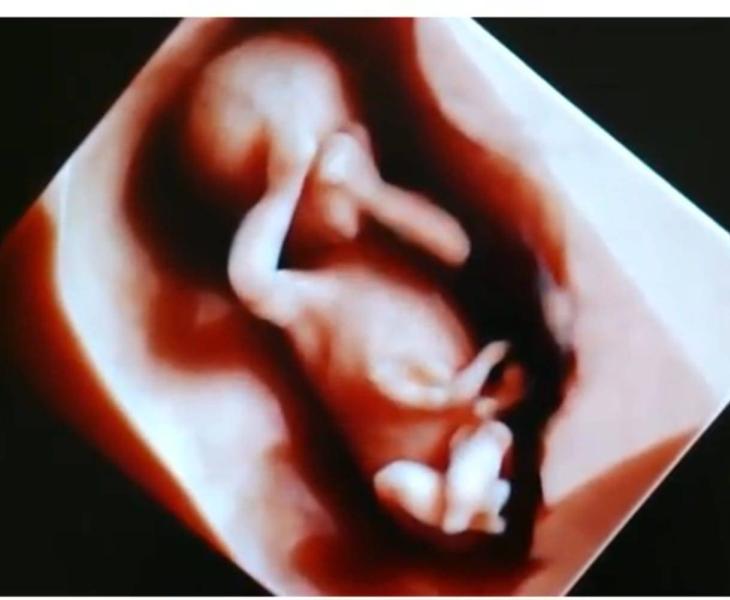

Я работаю на узи с 2007 г, т.е. уже 18 лет. 3д делаю с 2015 г, т.е. 10 лет.

Сейчас покажу фотки с 2015 ,2016 ,2018 гг.

И они нисколечко не уступают по красоте и качеству сделанным сегодня или вчера .

Если не нравится, проходите мимо. Мне очень нравится, поэтому делюсь . Это самое милое и очаровательное, что есть в этом мире . 😍